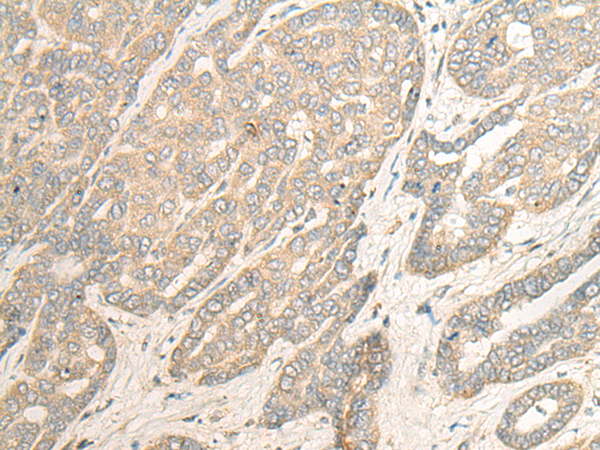

分类: 科研抗体货号: P09632别名: VIB1B; PtdInsTP; PI-TP-beta应用: WB,IHC反应种属: Human, Mouse, Rat